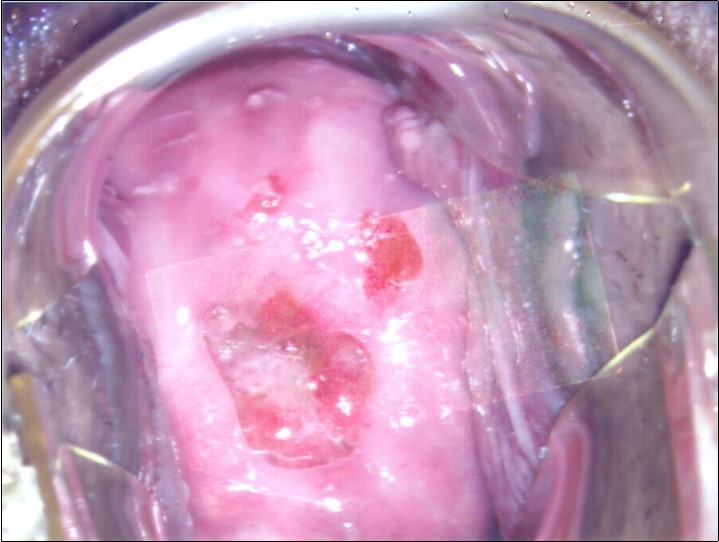

At initial presentation, colposcopy was unsatisfactory due to inadequate visualisation of the transformation zone. (Figure 1) Severe cervico-vaginitis was seen, with frothy white discharge and contact bleeding. A small focus of aceto-white epithelium was seen at the 1 o’clock region surrounded by peeling, friable epithelium. HPV DNA test, as well as cervical punch biopsy of the focus of aceto-white epithelium were taken.

Figure 1.Initial colposcopy

Initial colposcopy